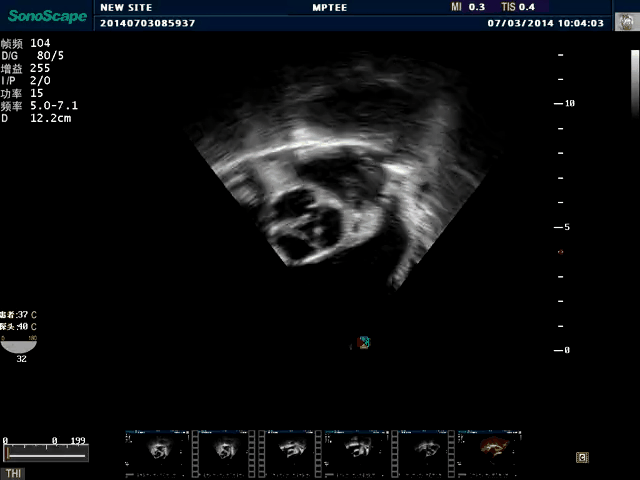

TEE(经食道超声心动图)将超声探头置入食道内,从心脏的后方向前近距离探查其结构 ,克服了经胸超声检查的局限性,避免肺内气体、胸壁脂肪、胸廓畸形等因素影响,观察角度更多,图像更加清晰,测量数据更准确。

经食道超声 大动脉短轴